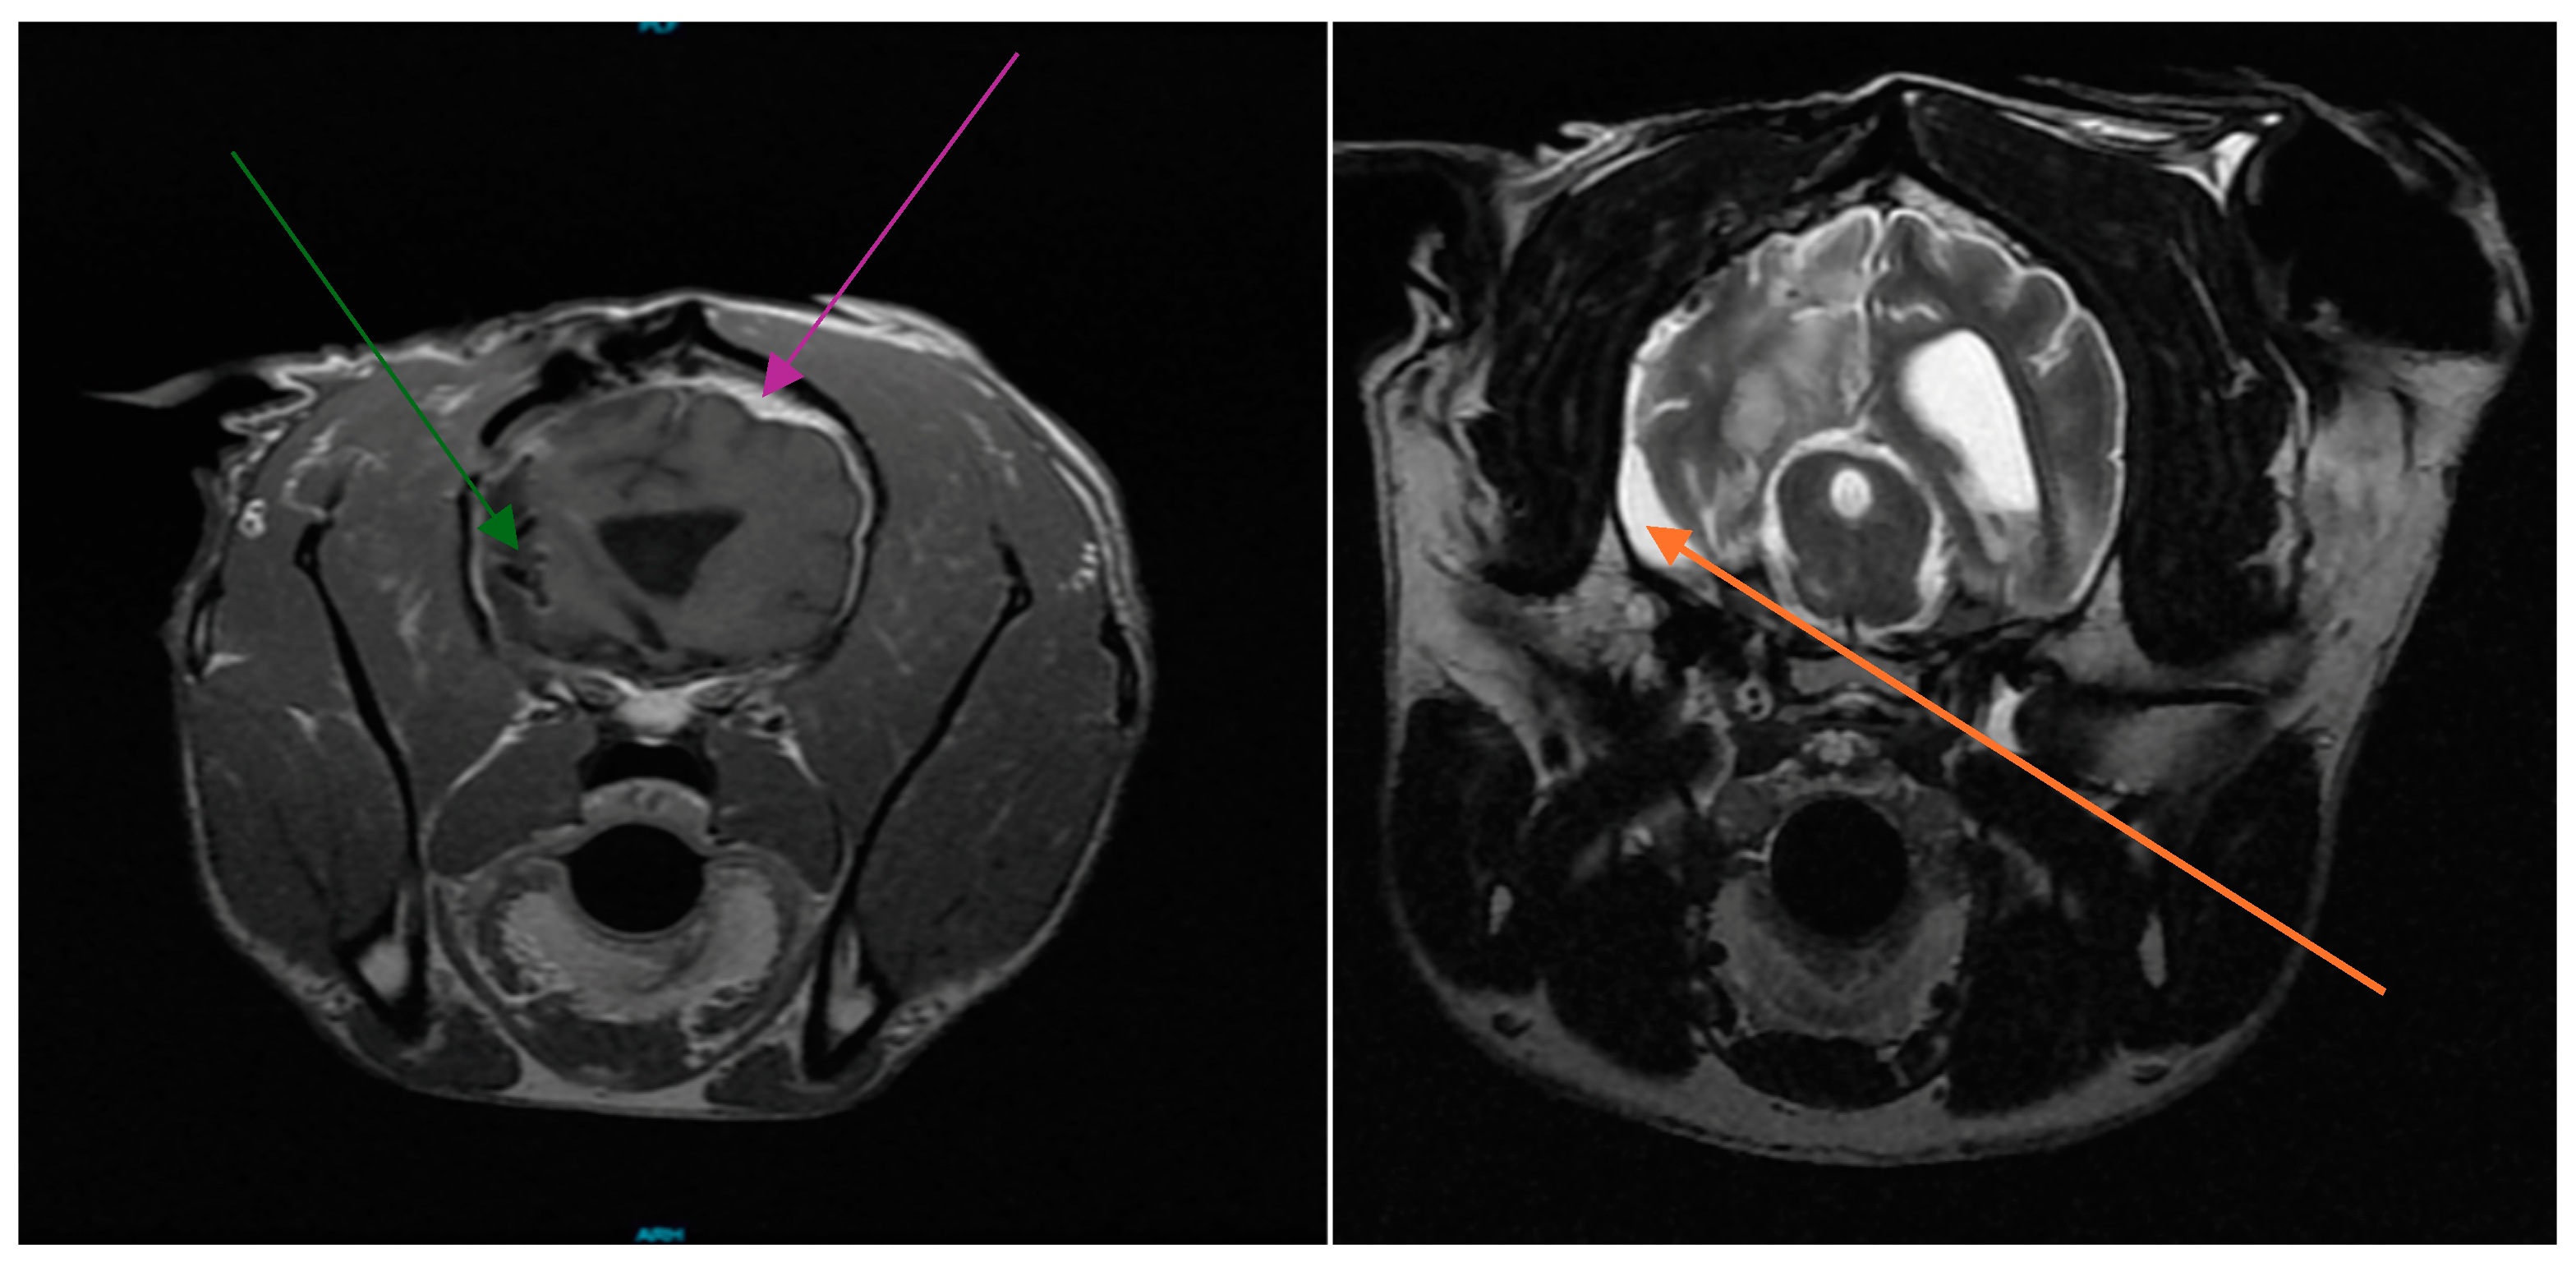

3.1. Patient History

3.2. Cesium Brachytherapy